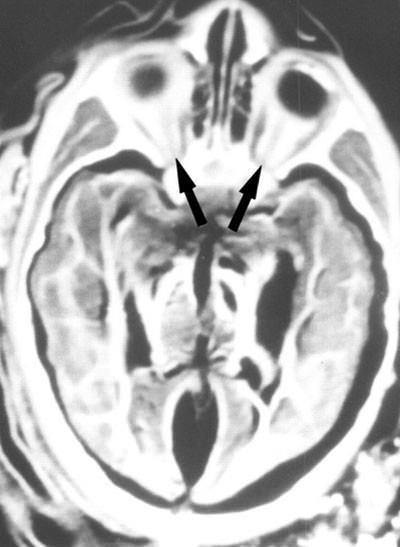

500 yıllık mumyanın ölüm sırrı